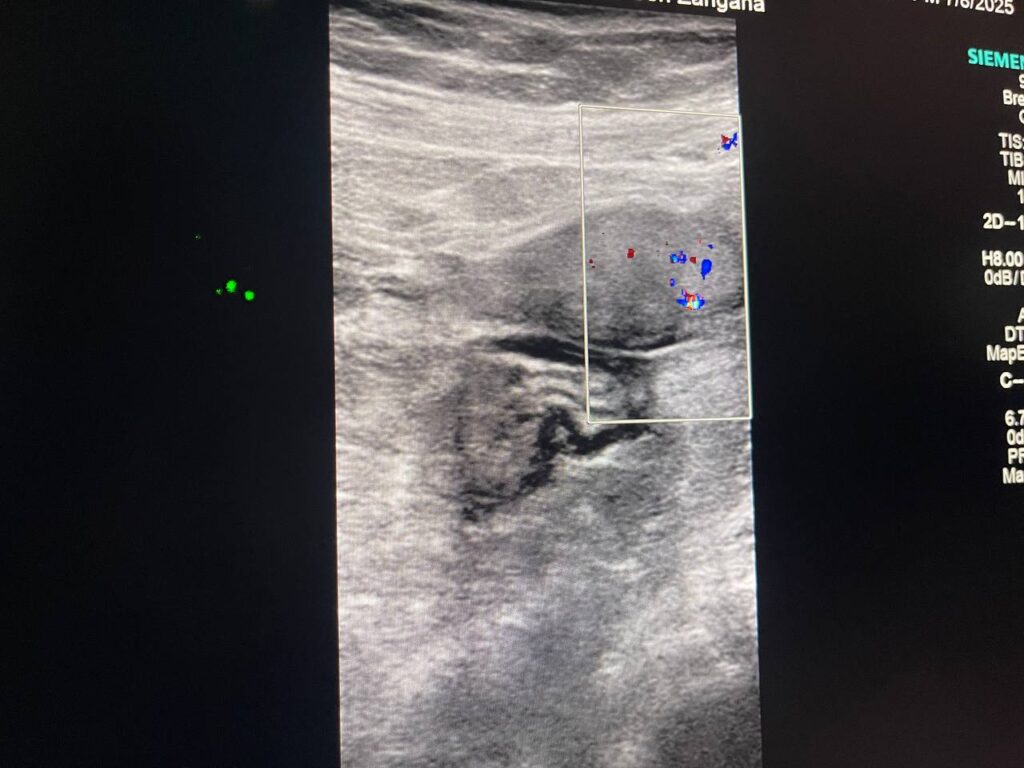

Presence of vascular (color score 3 ) hyperechoic mass 15x14mm , within the right ovary , please for further study